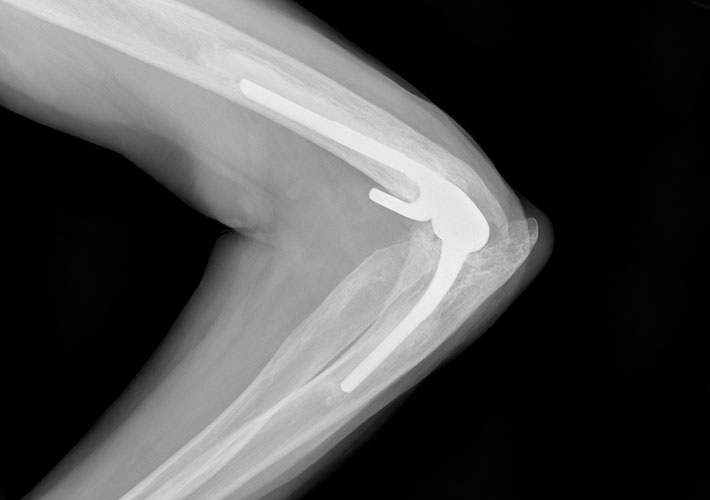

ASTM International’s committee on medical and surgical materials and devices (F04) has updated its standard on elbow prostheses to include testing guidance. This is the first time that any standards organization in the world has incorporated testing into a specification for these products, according to the committee.

The revision to the specification for total elbow prostheses (F2887) will help manufacturers, regulatory bodies, and test laboratories, according to Brian Kincaid, an ASTM International member. These groups will benefit from the testing guidance to help objectively evaluate the safety and efficacy of total elbow replacement (TER) devices under laboratory conditions that are commonplace for other large total joints.

“These updates provide references to peer-reviewed literature that describes bench-top testing methodologies in detail, and address the many performance requirements in F2887,” says Kincaid, a manager at Zimmer Biomet. “Prior to this revision, the specification had no specific testing guidance. These methods in totality represent the first such testing standards for TER devices worldwide.”

According to Kincaid, this update will help foster benchmarking of safety and efficacy for new TER designs, with the goal of better clinical outcomes and higher patient satisfaction.

The methods described in the standard are specific to the “linked semi-constrained” style of TER. Kincaid says the committee welcomes anyone interested in helping integrate methods for other designs such as hemi and radial head.